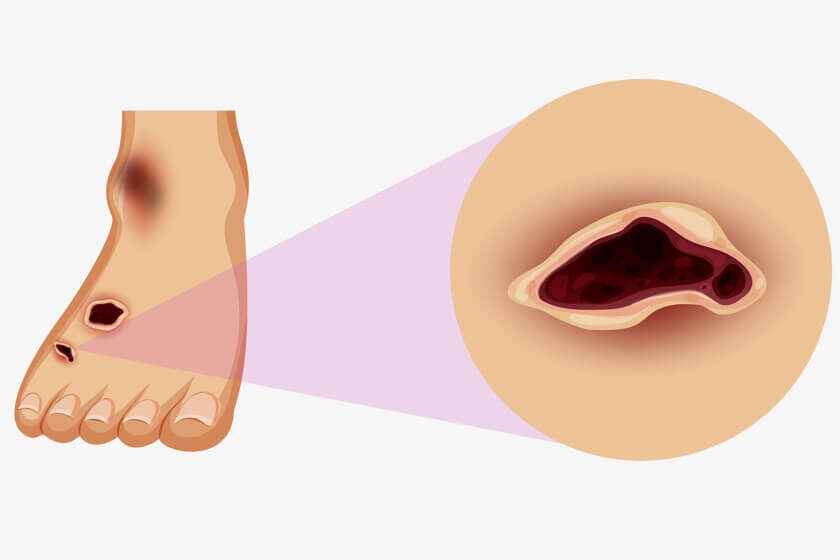

Symptoms of Arterial Ulcer

Arterial leg ulcers typically appear on the feet and lower legs. They are usually small, round, and deep, with a defined edge. The skin around the ulcer may be shiny, dry, and discolored. The ulcer may be painful, especially when the leg is elevated. In severe cases, the ulcer may be surrounded by blackened or necrotic tissue ( also popularly called as gangrene). Arterial leg ulcers are caused by poor blood flow in the arteries that supply the legs. This poor blood flow can lead to tissue damage and the development of a non-healing sore, which can eventually become an ulcer. The symptoms of arterial leg ulcers may include:

Non-healing sore:

The ulcer may be open and weeping, with a yellow or brownish crust. It may be surrounded by a red, purple or blackish border.